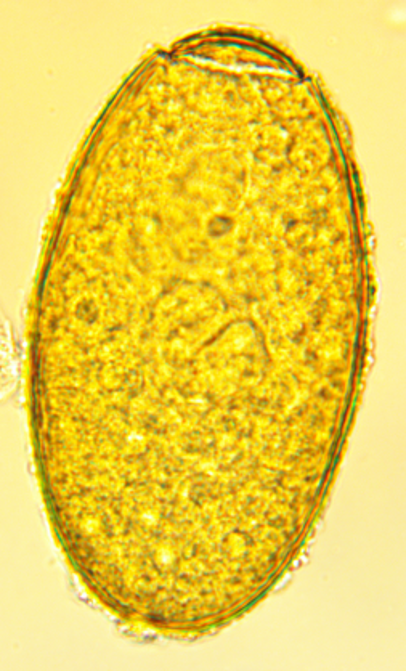

Fasciola hepatica

Common name: Liver fluke

DH: Cattle, sheep, goats

IH: Freshwater snails

Loc: Liver, bile ducts

LC: Indirect — ingestion of metacercariae on vegetation

CS: Anemia, weight loss, diarrhea, hepatomegaly, bottle jaw

DX: Fecal sedimentation (eggs), serology, liver necropsy

TX: Triclabendazole, Albendazole

PREV: Drain wet pastures, control snails, rotate grazing

ZOON: Yes (rare; humans)